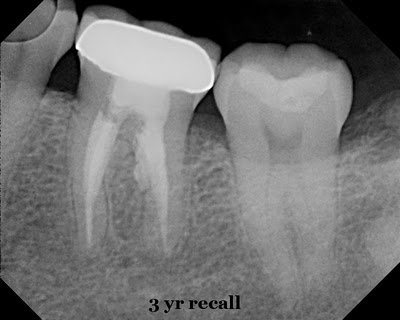

3 year recall (since the retx and repair with MTA) shows complete healing of the furcal lesion. The tooth is fully functional and asymptomatic. This is a tooth was was saved by endodontic therapy using the right material. This tooth was saved by endodontic therapy and the use of MTA to repair and seal the resorptive defect.